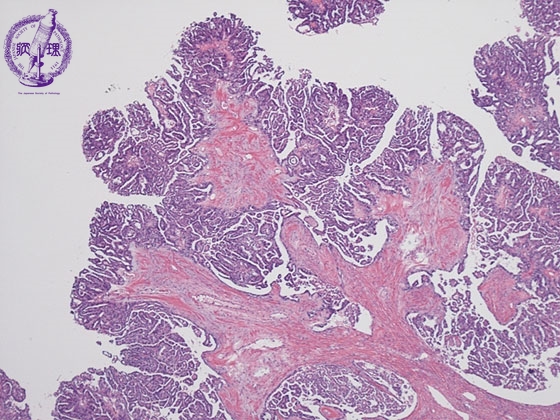

- (6)Serous adenocarcinoma of the ovary

Histology (HE stain, low power): Serous cystadenocarcinoma of the ovary. Small cuboidal carcinoma cells demonstrated papillary growth with fibrous stroma (yellow dotted line)